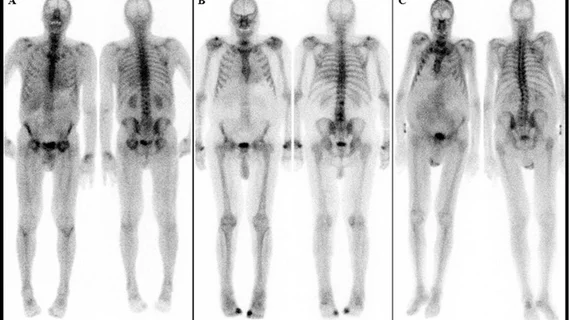

为应对PYP短缺,许多核实验室已开始尝试使用其他成像方法作为替代品。其中,Tc-99m羟甲基二膦酸盐(HMDP或HDP)成像被认为是一个可行的替代方案。尽管HMDP在ATTR成像方面的临床数据相对较少,但随着短缺的持续,越来越多的医疗中心开始使用HMDP,并收集相关研究数据以评估其效果。

Chareonthaitawee博士表示,HMDP和PYP在成像协议上存在一些差异,例如HMDP的摄取时间为1小时,而PYP为2到3小时,但两者的图像质量非常相似。她补充说,梅奥诊所正在通过使用HMDP收集研究数据,以进一步验证其作为替代品的可行性。